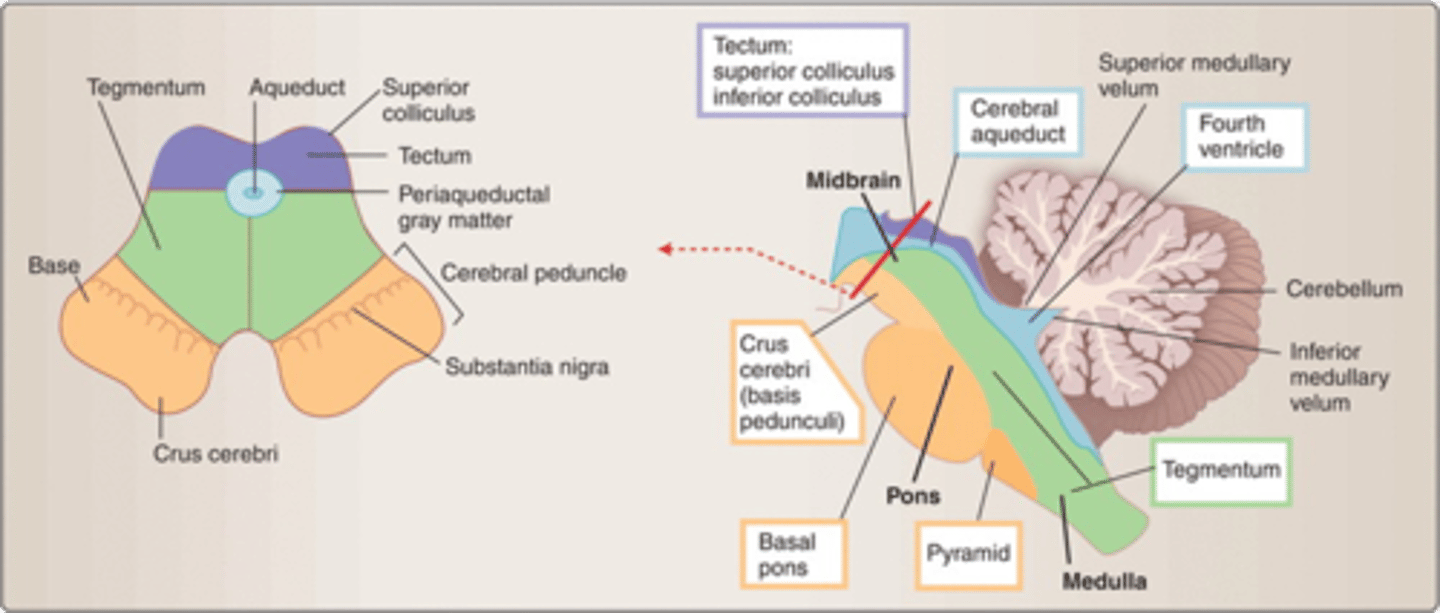

what are the 3 parts of the brainstem?

1. midbrain

2. pons

3. medulla

which region of the brainstem contains the cerebral penduncles? what is the ventral portion of the cerebral peduncles that contain corticospinal and corticobulbar fibers?

midbrain; crus cerebri

which region of the brainstem contains the cerebral aqueduct?

midbrain

looks like a hole in the center of the midbrain

cerebral aqueduct connects the 3rd and 4th ventricles

what region of the brainstem contains the cerebellar peduncles (to connect the cerebellum to the brainstem)?

pons

what medulla structure is a swelling along the ventral surface composed of motor fibers of corticospinal and corticobulbar tracts?

pyramid